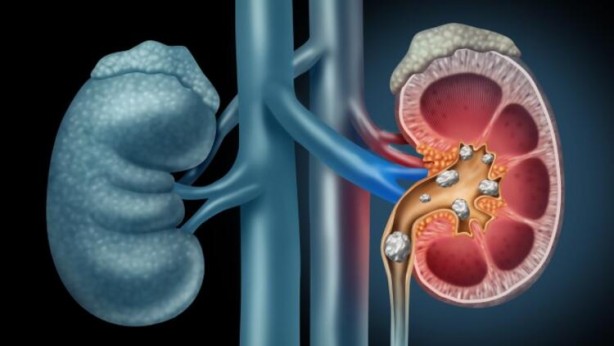

İçerdiği vitaminler sayesinde birçok faydası olan ve bu nedenle de sürekli tükettiğimiz limon suyu aslında çok da masum değil. Uzmanlar limon suyunun zararlarına ilişkin önemli araştırmaları ortaya koydu. İşte limon suyunun sebep olacağı rahatsızlıklar...